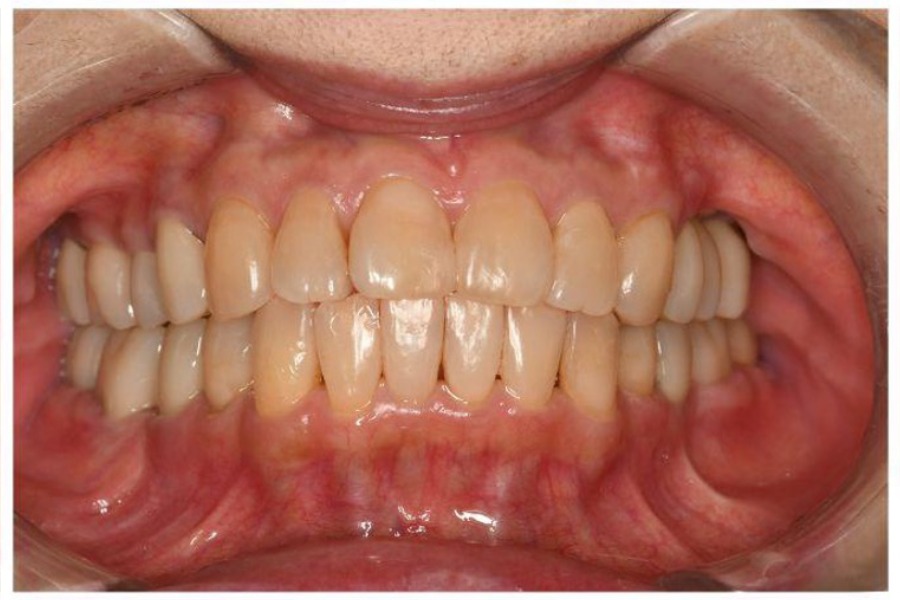

治療後